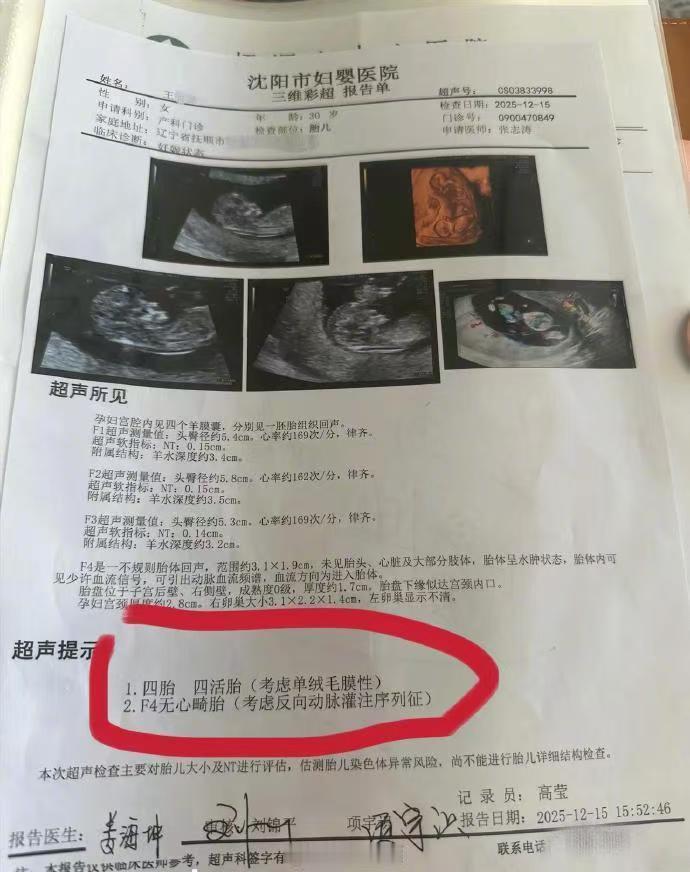

辽宁抚顺的一位准妈妈最近经历了人生中过山车般的时刻。怀孕16周的王女士,原本只是按部就班地进行产检,却在医院拿到了一份极其罕见的诊断报告。从去年11月到12月,短短一个月的时间里,她在医院进行了四次产检,每一次彩超单上的图像都在发生变化——最终确认,她怀上了四胞胎。 这并非普通的四胞胎。根据相关医生的诊断,王女士怀上的是同卵四胞胎。在医学领域,同卵四胞胎的发生率极低,属于非常罕见的个案。更复杂的情况在于,医生指出第四个胎儿为“无心畸胎”。这是一个专业性很强的术语,意味着这个胎儿虽然没有正常的心脏发育,但依然依赖其他胎儿的血液循环在母体内生存。这种特殊的医学状况,无疑给整个孕期增添了巨大的不确定性和风险。 对于普通家庭而言,多胞胎往往意味着双倍的喜悦,但在医学视角下,这更多代表着高风险妊娠。从数据来看,自然受孕情况下同卵四胞胎本就凤毛麟角,而伴随无心畸胎的情况更是让保胎之路布满荆棘。王女士在抚顺当地医院进行的这四次检查,实际上是一个不断排查和确认的过程。每一次彩超,不仅是在数胎儿的数量,更是在评估母体和每一个胎儿的生存质量。 网友们对此议论纷纷,有人感叹生命的奇妙与不易,也有人为即将到来的抚养压力感到担忧。毕竟,四个孩子的降生,对家庭的经济状况、父母的精力都是极大的考验。目前摆在王女士和家人面前的,不仅是喜悦,还有如何根据医生的专业建议,制定最科学、最安全的后续妊娠方案。 这起事件也给广大备孕及孕期女性提了个醒:规范的产检流程至关重要。像王女士这样,通过连续、定期的超声检查,才能及时发现多胎妊娠及胎儿发育异常等特殊情况。面对罕见病例,医学干预和监测是保障母婴安全的最有效手段。祝愿这位准妈妈能平安度过接下来的孕期,也希望这个小生命群体能在现代医学的保驾护航下,迎来最好的结局。 以上内容仅供参考和借鉴